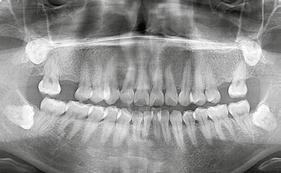

en paciente adulto tratado con extracciones de primeros molares permanentes. Reporte de caso

Dentista y Paciente 52 Sonriendo al futuro